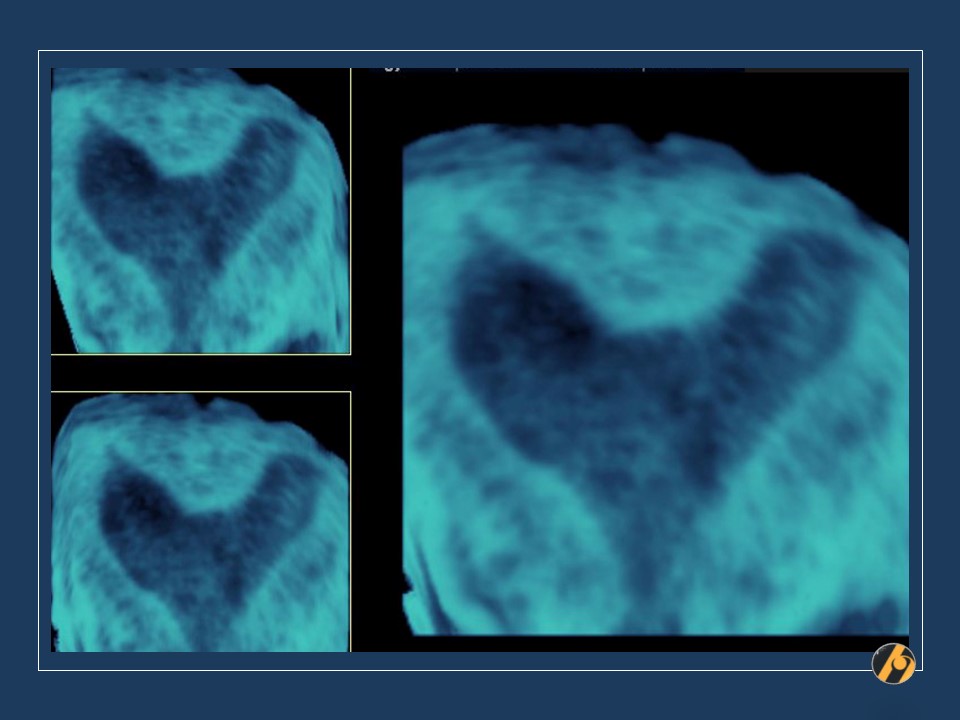

Kontrastna sonohisterografija / 3D multiplanarni prikaz

Kontrastna sonohisterografija / ubrizgavanje sterilne fiziološke otopine u materničnu šupljinu prilikom ultrazvučnog pregleda, prikazuje dvorogu maternicu. Za razliku od septirane maternice, ovdje je fundus uleknut između dva tijela maternice, što ukazuje na dvorogu maternicu. U tom slučaju, Müllerove cijevi se tijekom embriogeneze nisu spojile niti u jednom dijelu materničnog tijela, a u donjem uterinom segmentu međusobno komuniciraju. Postoji samo jedan vrat maternice. U slučaju 2 cerviksa, anomalija se naziva uterus didelfis. U ovom slučaju je bilo kakva operativna intervencija pogrešna jer se dvije maternice ne mogu spojiti na kvalitetan način koji bi omogućio plodnost. Zanošenje ne predstavlja problem, jer je prokrvljenost svih dijelova materničnih stijenka uredna. Poblemi se javljaju u vidu krvarenja iz drugog roga maternice tijekom rane trudnoće, koja na sreću najčešće ne dovode do spontanog pobačaja. Prijevremeni porod je češći nego u općoj populaciji.